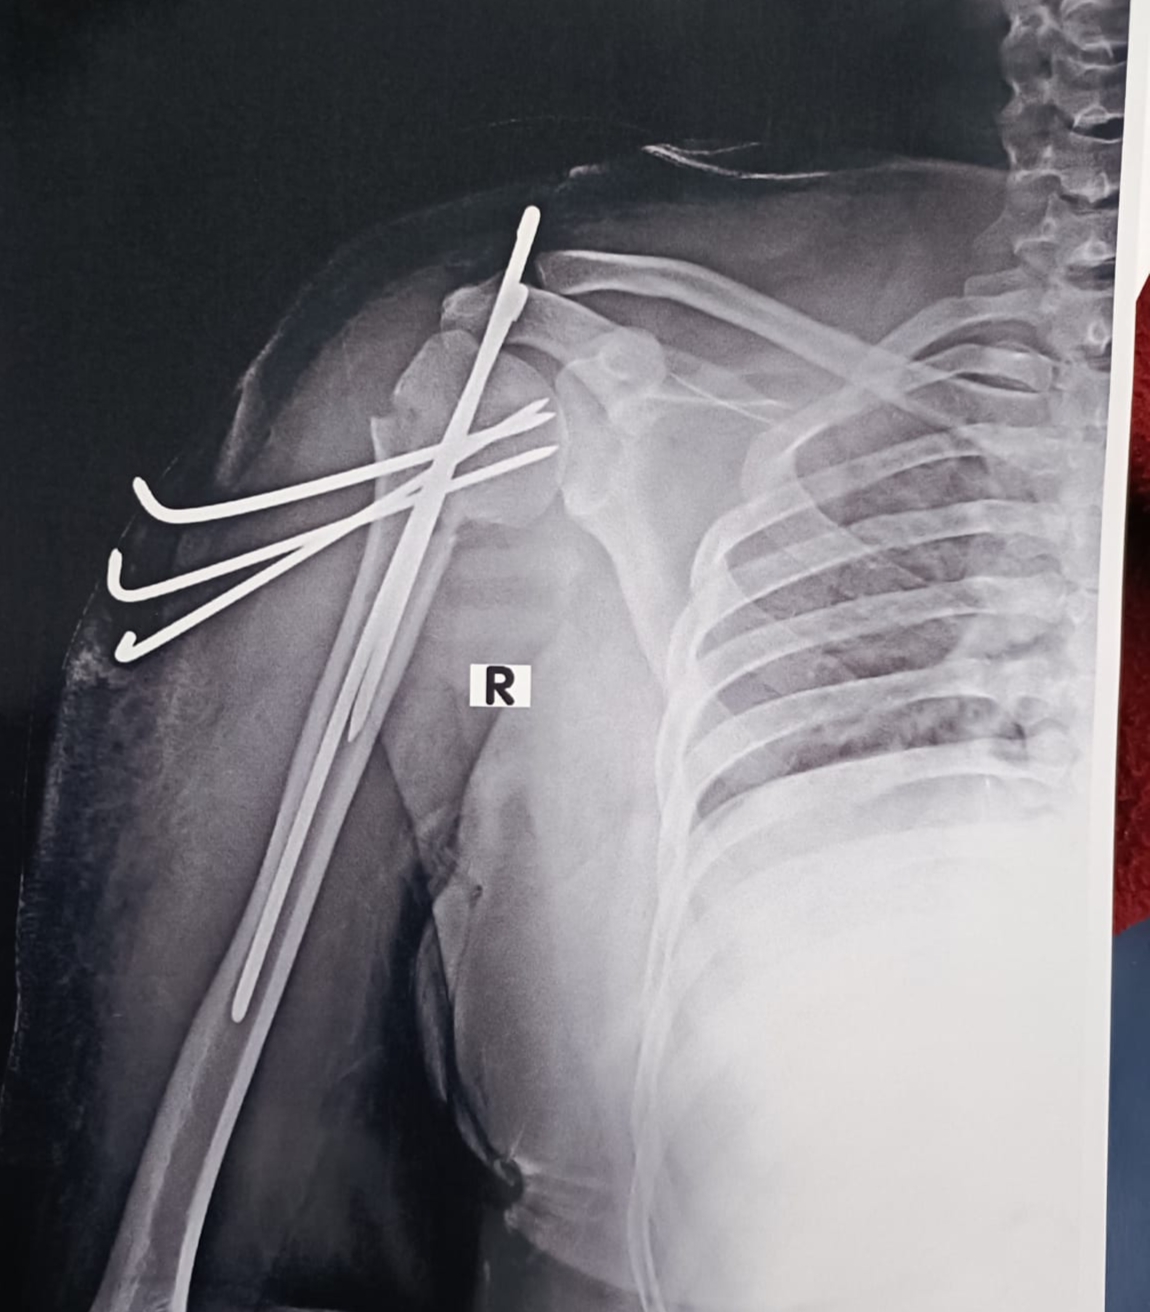

shoulder bone break h opretion hua h 4 tar dake dale gye h

Isko recover hone m kitna time lgega kya y phle jesa ho jayega age 20 year h bone break h give me advise sir what I do